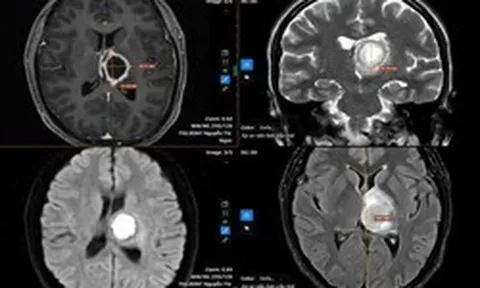

Anh Triệu Minh Tuấn, cán bộ Đội Chữa cháy và Cứu nạn cứu hộ khu vực 6, Phòng Cảnh sát PCCC và CNCH Công an tỉnh Thanh Hóa (giữa) trả lại người chuyển nhầm

Sau khi xác minh đúng chủ nhân của số tiền chuyển khoản nhầm, chiều 13-3, dưới sự chứng kiến của các cơ quan chức năng, anh Triệu Minh Tuấn đã trực tiếp bàn giao đầy đủ số tiền cho anh Đỗ Viết T..